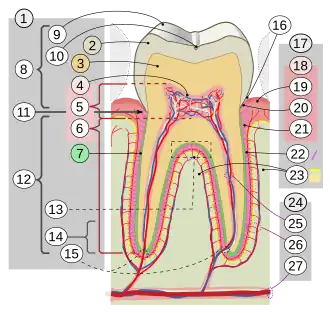

Pueden distinguirse siete partes distintas en el diente (1): 2. Esmalte | ||

| Componentes |

• Esmalte • Dentina • Pulpa • Cemento • Membrana alveolar • Hueso alveolar | |

La estructura general es similar en las diferentes especies, aunque hay una variedad considerable en su forma y posición. Todos los dientes poseen pulpa dentaria, algún tipo de dentina y, en la parte más externa, esmalte, a excepción de los condrictios que poseen una sustancia similar al esmalte o esmaltoide.[3] Los dientes de los mamíferos tienen raíces profundas, las que también se encuentran en algunos peces y cocodrilos.